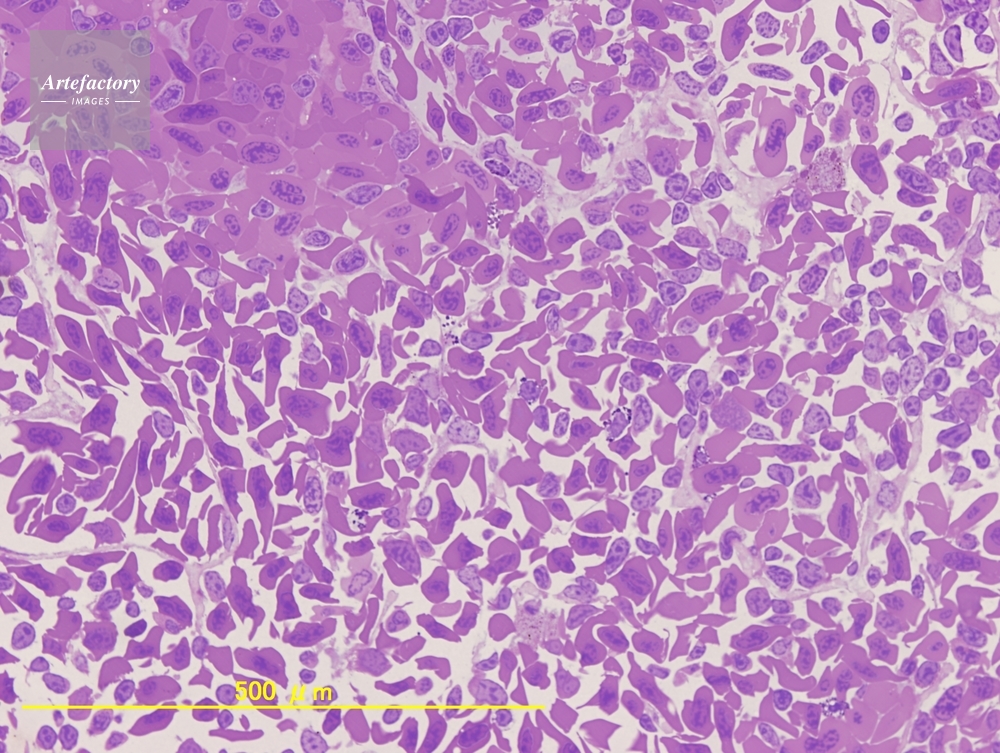

| 作品タイトル | イモリ 脾臓 | モデルリリース | なし | |

| 作家 | OLYMPUS CORPORATION Technolab | プロパティリリース | なし | |